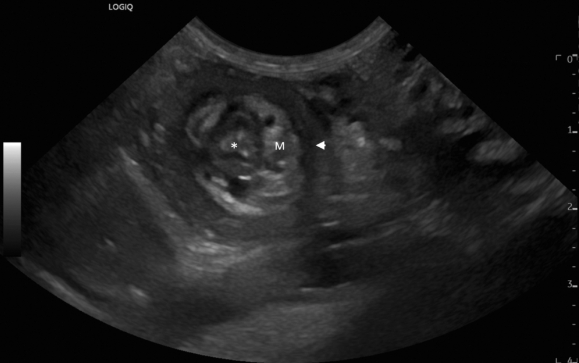

그간 개에서 회맹장 중첩이 발생하는 경우 수술적으로 접근하여 치료하는게 일반적인 방법이었다.

거의 대부분의 수의사들도 사람 소아과에서는 중적이 발생했을때 관장을 통해 치료한다는 사실을 알고는 있었지만

쉬 개에서 적용하지 못했던 이유는 그 시술이 비록 소아과에서는 적용되었던 시술이나

개에서는 적용해도 되는지에 대한 근거가 부족했기 때문이다.

그런데 이제 근거 논문이 나왔으니

1케이스에 대한 증례이나 이를 근거로 시도로 인해 발생하는 문제에 대한 법적 소송을 대응할 근거가 마련되었다고 할 수 있겠다.

물론 단일 케이스이니 충분한 부작용에 대한 연구는 후향적으로 더 필요할것이다.